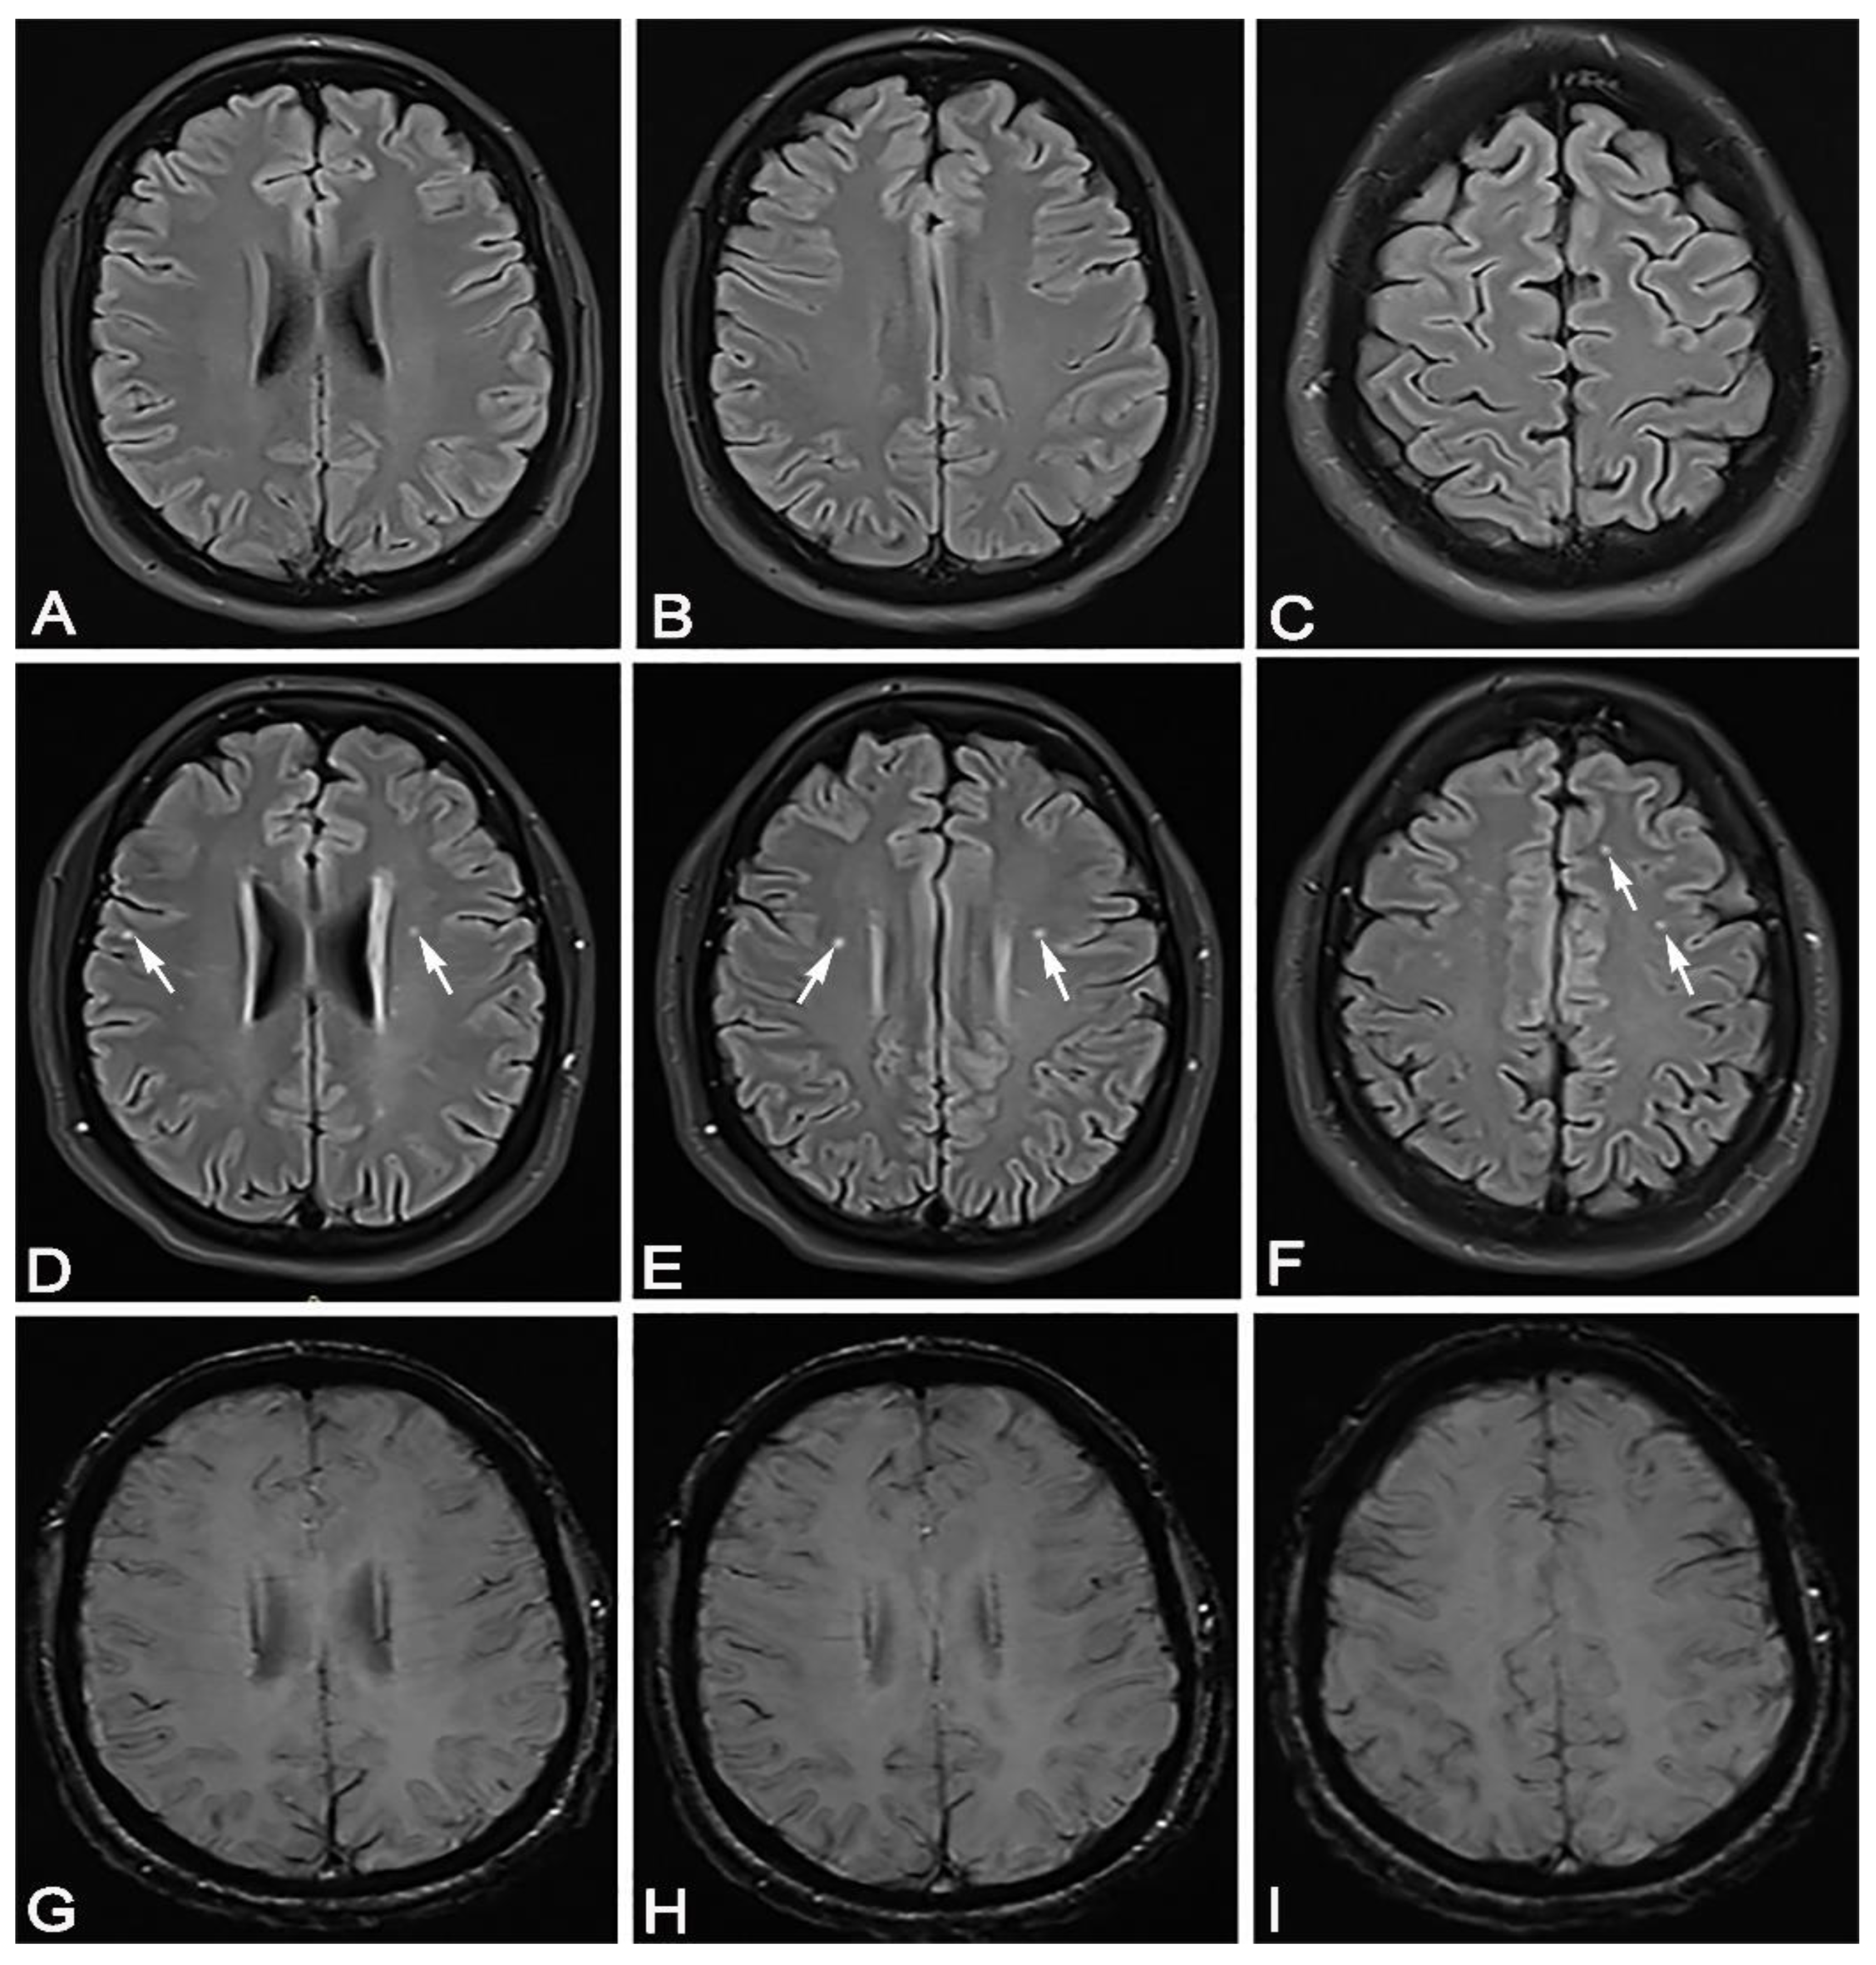

Figure 3. In April 2020, a 35-year-old female patient came for a brain MRI due to vertigo. (AC) She showed completely normal brain MRI. In February 2021, 50 days after recovering from mild SARS-CoV-2 infection, the same patient came for a brain MRI due to headache, vertigo and taste and smell disorder. (DF) She showed hyperintense lesions on FLAIR sequence, periventricular bilaterally, bifrontal subcortical and right juxtacortical (white arrows). The same transverse cross sections of the FLAIR sequence as on (AC), without signs of microhemorrhage on the SWI sequence (GI).

The location of the lesion is also evident in patients with mild and moderate forms of the disease in three locations: bilateral periventricular, bilateral frontal subcortical and bilateral frontoparietal juxtacortical. In both groups of patients, the lesions are statistically significantly grouped mostly bilaterally frontally subcortically, then bilaterally periventricularly. There was a statistically significant difference in the number of lesions at both sites in patients who had overcome a moderate form of SARS-CoV-2 infection. We considered it very important to emphasize that in both groups of patients, a higher number of lesions was bilateral frontally subcortical than bilaterally periventricularly, and significantly more in patients who had a moderate form of the disease. (Figure 3). SARS-CoV-2 shows similarities with SARS-CoV, which enters the CNS, as evidenced by preclinical and postmortem studies [24]. In our study, in both groups of patients, most of the lesions were located bilaterally frontally subcortically, and in the postmortem study, a virus was detected inside the frontal lobe [25]. The lesions were located mostly within the white matter and did not show the character of demyelination, although in their study, Zanin et al. showed patients with numerous confluent periventricular demyelinating lesions [26]. Therefore, this points to differences in brain MRI findings.